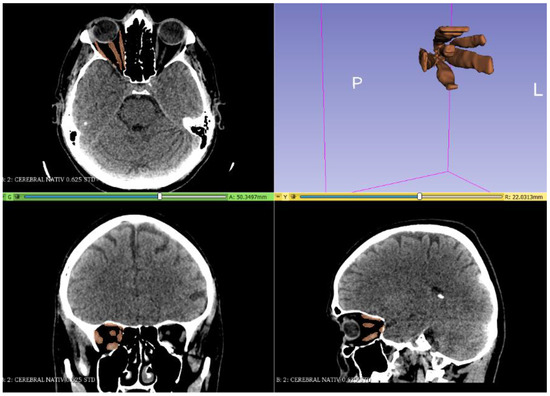

2. Materials and Methods

3. Results